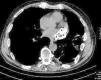

Doente do sexo masculino, de 69 anos, com antecedentes de hipertensão arterial, dislipidemia, AVC em 1995 e traumatismo toraco‐abdominal esquerdo em 1999, após embate com boi, do qual resultou hemopneumotórax. Trata‐se de um doente referenciado à consulta de cardiologia após deteção acidental numa tomografia computadorizada (TC) toraco‐abdominal de uma extensa área (54×36×20mm) com calcificações lineares irregulares localizada posteriormente dentro do saco pericárdico, em posição alta (Figura 1). Para esclarecimento adicional da natureza intra/extravascular da calcificação e despiste de lesão tumoral foi pedido um ecocardiograma transtorácico, transesofágico e uma angio‐TC torácica.